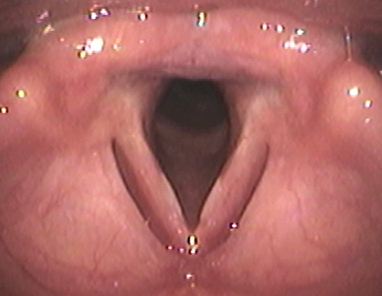

(6) 성대 질환

성대 질환은 성대의 구조적 문제로 인해 발생할 수 있습니다. 성대 결절 외에도 성대 용종이나 성대 마비와 같은 질환이 있으며, 이들 역시 목소리를 쉬게 만들 수 있습니다.

(2) 성대 결절

성대 결절은 성대에 생기는 작은 혹으로, 주로 과도한 목소리 사용으로 인해 발생합니다. 이 결절은 성대의 진동을 방해하여 목소리가 잠기거나 갈라지게 만듭니다.